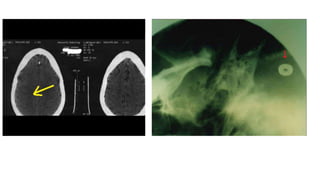

A partir dos anos 1960, começaram

a aparecer pessoas com estranhas

marcas no corpo: cicatrizes,

pequenas cavidades, cortes por laser

em série.

São o resultado de cirurgias,

desinfecção, retirada de fluidos,

inserção de microchips...

Marcas nos abduzidos Apartir dos anos 1960, começaram a aparecer pessoas com estranhas marcas no corpo: cicatrizes, pequenas cavidades, cortes por laser em série. Tornozelo, pulso, costas, quadris, seios etc. São o resultado de cirurgias, desinfecção, retirada de fluidos, inserção de microchips...

mais de 50milhões de IMPLANTES ALIENÍGENAS em todo o mundo Implantes são microchips que servem para: - Rastreamento/monitoramento - Controle mental - Aperfeiçoamento genético/energético

Este tipo deimplante é encontrado em inúmeros abduzidos